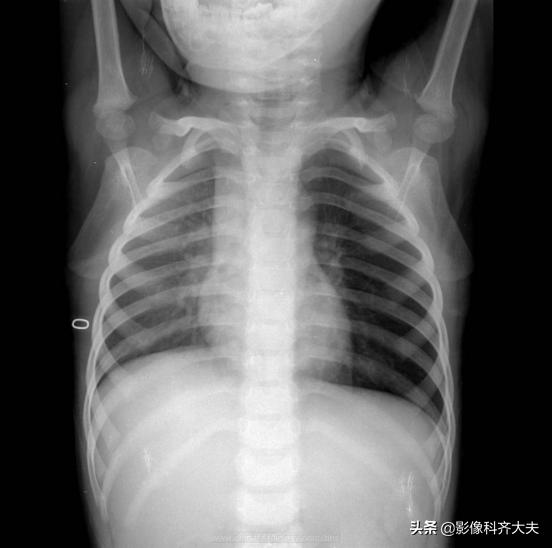

图为正位普通X线片,显示左侧明显肺气肿改变,提示左侧支气管异物可能,因家属否认异物吸入,遂进一步做CT确诊。

CT冠状位重建明确显示左侧自气管阻塞,有明确异物的存在,红色箭头所示。